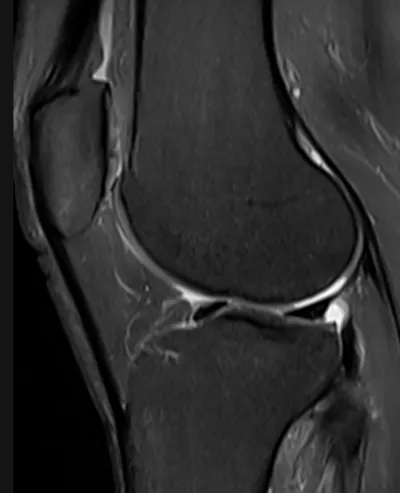

Cartilage Radiology Images

Browse 4 medical images tagged with cartilage. This collection includes various imaging modalities for medical education and reference.

- This collection contains 4 radiology images related to cartilage, including various imaging modalities such as X-rays, MRIs, CT scans, and ultrasound images commonly used in medical diagnosis and education.